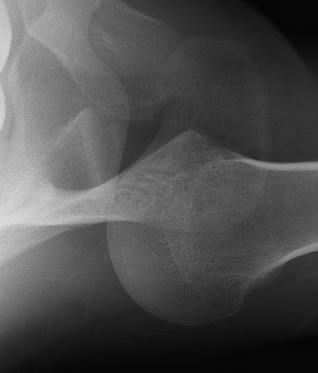

AP Xray

Abnormal overlap of humeral head on glenoid

Light-bulb sign - globular head secondary to internal rotation of the humeral head

Vacant Glenoid Cavity - > 6 mm space between humeral head and anterior rim of glenoid